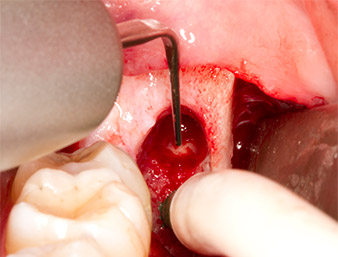

Using an instrument for periodontal debridement (Piezomed P1), the periodontal ligament space of the radix relicta was then widened minimally (Fig. 8).

The same activated instrument was inserted into the root canal and loosened the fragment as a result of its micro-oscillating vibrations (Fig. 9, 10).